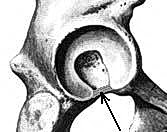

| Рис.3.49 Поперечная связка вертлужной впадины, показана стрелкой. |

По мнению А.П.Сорокина (1973) ПСВВ возникает вследствие расхождения костей и работает «на растяжение». Она появляется уже у эмбриона длиной 20 мм (Голуб Д.М., Бронивицкая Г.М., 1981). ПСВВ представляет собой плоский тяж. Есть мнение о том, что ПСВВ образована волокнами вертлужной губы, которые перекидываются через ВВВ (Кованов В.В., Травин А.А. 1963). Согласно же Б.З.Перлину и соавт. (1977) элементы ПСВВ вплетаются в вертлужную губу, будучи почти в два раза ее шире и несколько толще. Ее передний конец прикрепляется к переднему краю полулунной поверхности, к заднему краю которой прикрепляется задний конец ПСВВ. При этом ПСВВ, подобно подвесному мосту, перекидывается через ВВВ в ее периферическом отделе (Рис.3.19). К наружному краю ПСВВ прикрепляется вертлужная губа, а внутренний край, обращенный в сторону ЯВВ, является свободным. Наружная поверхность ПСВВ – вогнутая и контактирует с гиалиновой оболочкой ГБК, внутренняя обращена в сторону дна ВВВ. Длина ПСВВ равна расстоянию между передним и задними краями полулунной поверхности в периферическом отделе ВВВ.